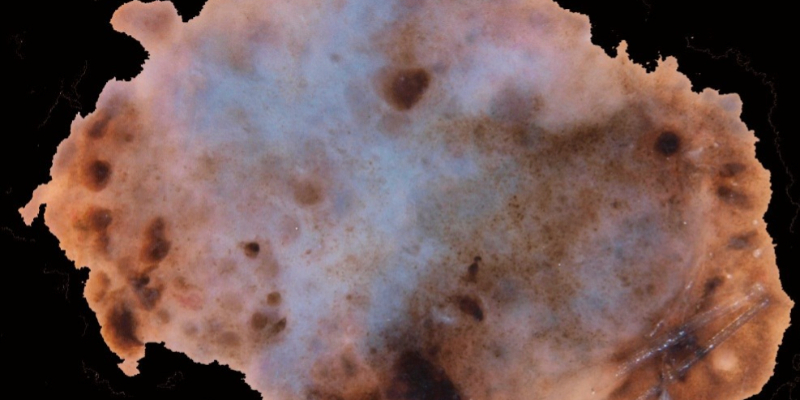

This unit covers the fundamental principles of the Chaos and Clues algorithm, a simplified yet effective decision-making tool for assessing skin lesions. Participants will learn to identify chaos in a lesion, which indicates the need for further examination, and recognise specific clues that suggest malignancy. The unit emphasises practical applications of the method and provides numerous clinical examples to help learners understand how to distinguish between benign and suspicious lesions.

In this unit, participants delve deeper into real-world case studies, applying the Chaos and Clues method to various pigmented skin lesions, including melanomas, pigmented BCCs, and SCCs. Through interactive case discussions, learners will assess clinical scenarios, identify the presence of chaos or clues, and determine whether to biopsy the lesion. The course also addresses exceptions to the method and offers strategies for handling complex or borderline cases​.